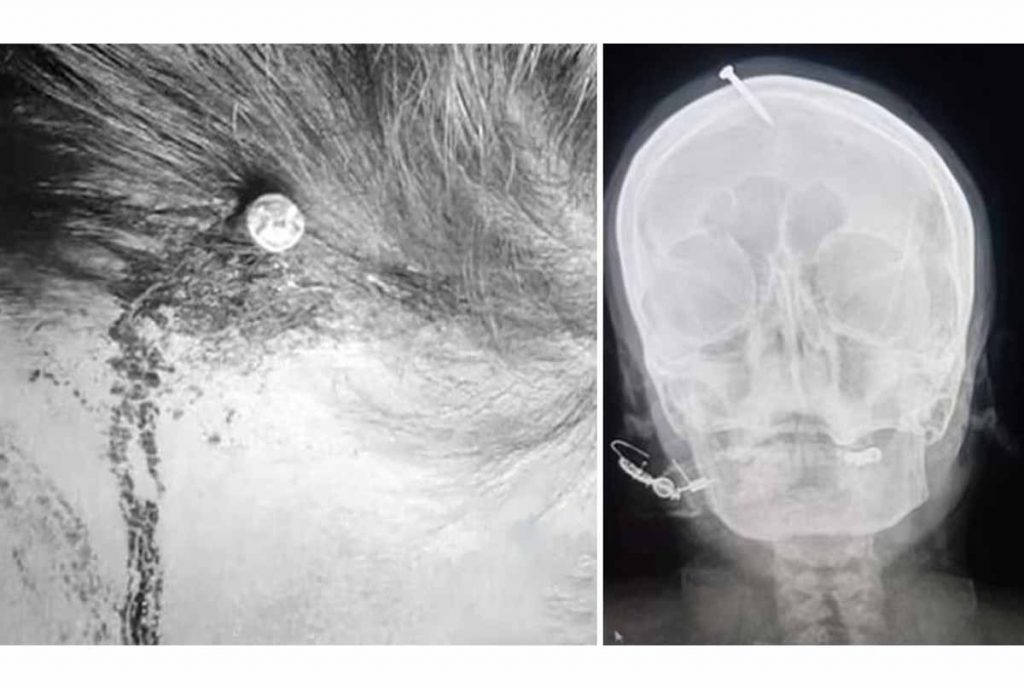

पाकिस्तानमा छोरा जन्माउने आशमा गर्भवती महिलाको टाउकोमा २ इन्च लामो किला ठोकिए छ। पाकिस्ताको पेशावर शहरमा रहेको लेडी रिडिङ अस्पतालमा एक महिला उपचारका लागि भर्ना भइन्। उनको टाउकोमा २ इन्च लामो किला गाडिएको थियो।

डेली मेलमा प्रकाशित समाचार अनुसार सुरुमा उनले अस्पतालका कर्मचारीसँग दुर्घटनावस किला गाडिएको बताएकी थिइन्। पछि उनले एक धार्मिक उपचारकको सल्लाहमा छोरा जन्मने विश्वासका कारण आफैं किला ठोक्न लगाएको स्वीकारिन्।

त्यसबाट डराएकी ती महिलाले छोरा जन्मने विश्वासमा टाउकोमा किला ठोक्न लगाएको समाचारमा उल्लेख छ। सुरुमा आफैँले किला निकाल्न प्रयास गरेर नसकेपछि मात्रै महिला अस्पताल आएको उक्त अस्पतालका डाक्टर हैदर खानले जानकारी दिएका छन्।

उक्त किला हम्बर वा कुनै गह्रो वस्तुले ठोकेर टाउकोमा लगाडेको देखिएको डाक्टर खानले बताएका छन्।